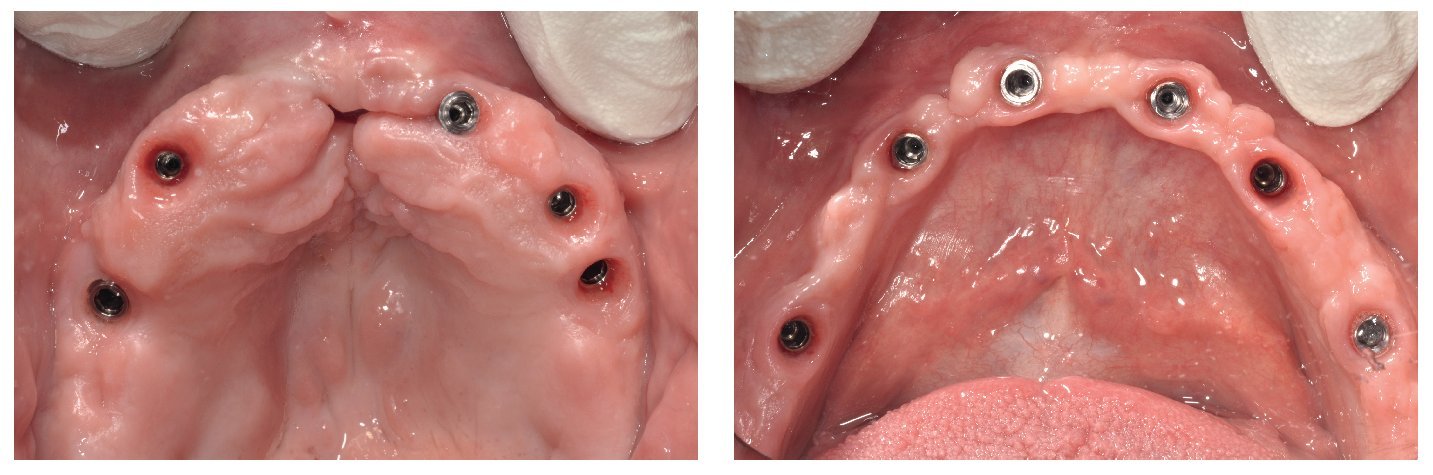

Para la rehabilitación definitiva del paciente (figs. 116 a 124) deben comprobarse de nuevo todos los aspectos de la sesión anterior y debe procederse a la cementación de las prótesis. Son indispensables controles de seguimiento a corto plazo (al cabo de 1, 3 y 5 semanas) para el ajuste óptimo de la oclusión y la comprobación de la higiene oral con una prótesis que habitualmente ofrece aberturas de acceso periimplantares más estrechas que una prótesis provisional. Tres y seis meses después de la finalización del tratamiento se deben realizar controles clínicos, y una vez al año deberían llevarse a cabo sendos controles clínico y otro radiológico.

Figs. 116 y 117. Las restauraciones definitivas fijadas a los implantes. Cabe destacar la buena curación del tejido blando periimplantar.